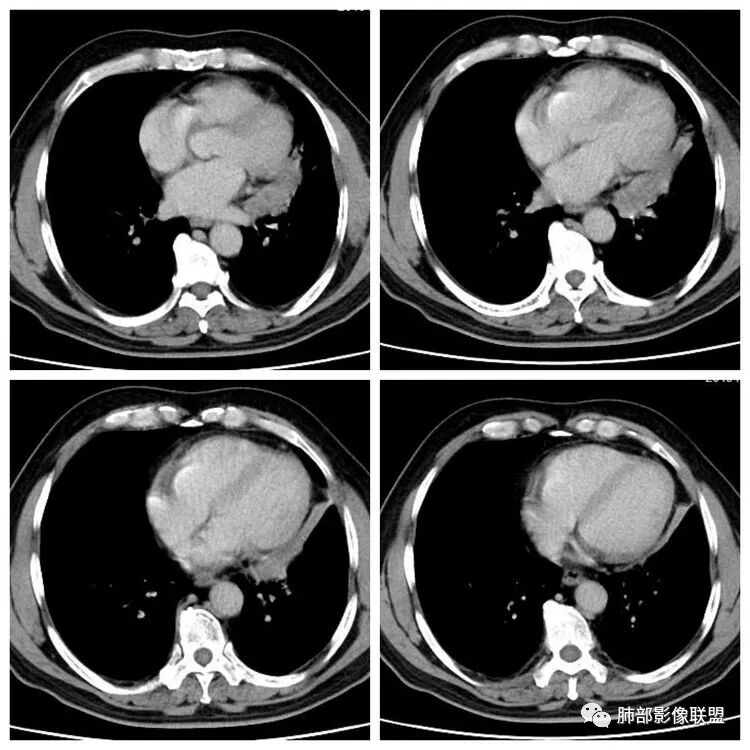

平扫 动脉期 静脉期  40HU、48HU、57HU

患者老年男性,“左肺占位”收入住院。查CEA轻度升高。胸部CT:左肺肺门占位并左肺下叶阻塞性,远端肺组织膨胀不全,增强可见轻度强化,内似见低密度灶。双肺多发类圆形结节,以左肺上叶尖后段为大,内可见部分钙化,边缘光滑、清楚。综合考虑恶性病变,鳞癌并转移可能大,鉴别腺癌、结核。

尘缘:

左肺下叶结节支气管进入截断,远端肺不张,增强后坏死不均匀,肺癌明显,至于病理类型,鳞癌,小细胞,腺癌都有支持和不支持的地方,个人倾向于鳞癌可能,理由,纵隔淋巴结肿大不明显,远端阻塞性不张,支持小细胞的地方,坏死呈沼泽样,但纵隔无明显淋巴结肿大及冰冻表现。腺癌这种表现一般为低分化腺癌,但远端阻塞性不张及纵隔无明显淋巴结肿大不支持。

1.主病灶明显堵塞支气管,我觉得如果结核爬行,应该是外向内爬,这个我觉得是内向外堵塞,而且爬行的结核一般是肉芽肿,不是坏死,增强不会这么低,这个密度和强化比较符合一个坏死。最重要鉴别,结核的爬行是外向内,周围有树丫。这个是内向外,支气管堵塞且坏死明显,外周的堵塞性肺不张,没有树丫,所以主病灶考虑内向外,故结核爬行不太符合。而中央型腺癌不是没有,而是少,加上坏死这么明显,淋巴结转移不明显,故猜测鳞癌或者唾液腺肿瘤可能性比较大,因为后者也是支气管中央起源,强化比较弱的。腺癌和小细胞不太典型,类癌可以表现为支气管粘液栓,但是强化不够。

病例结果:2年前直肠癌根治术后改变,中分化腺癌,支气管镜检:转移性腺癌。

1.定位:左肺块影同时累及下舌段及下叶内基底段且相互延续。病灶跨叶,或存在叶裂发育异常,或者说就是病灶的肺门蔓延。

2.病灶前上部分与舌段支气管相关且形成阻塞。

3.左肺上叶另见孤立结节影,边界清楚光整,中央钙化,未见脂质密度特征。

4.增强扫描左肺门区块影轻度强化,强化程度轻于舌段周围不张肺组织。

6.分析:男性患者,左肺门区块状影,支气管阻塞,强化不显著,未见淋巴结肿大,更多见于肺鳞癌。难以解释的是下肺病灶的生长方式。

沿肺门或是叶裂缺损孤立发生且蔓延,转移性腺癌似乎可以解释,但占据较大支气管腔就属罕见了。

本例很难首先怀疑转移灶。

7.左肺上叶孤立小结节影中央钙化可见于肠道肿瘤,但更多见于错构瘤,或是结核球。